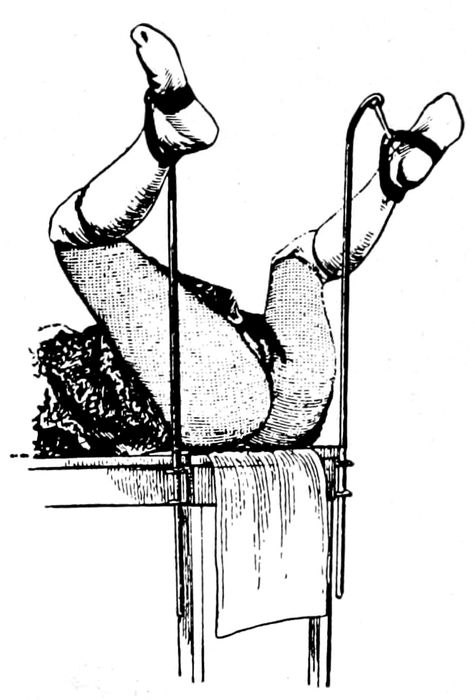

| 71. |

Exaggerated lithotomy position |

181 |

| |

| 72. |

Dorsal position when assistants are available |